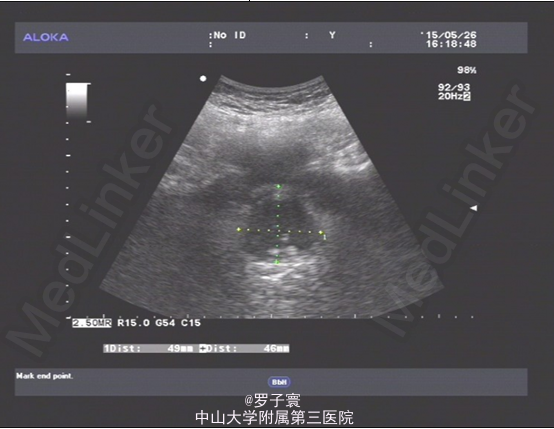

者入院完善相关检查:尿常规提示红细胞计数增高(RBC44个/ul),生化、凝血、术前筛查、肿瘤三项、PSA两项、性激素六项、血常规未见明显异常。泌尿系彩超:双肾集合系统回声增多,不排除小结石;双侧输尿管未见扩张;膀胱多发结石;前列腺增大,前列腺钙化斑;双侧精囊超声检查未见明显异常。腹部平片:考虑膀胱多发结石。